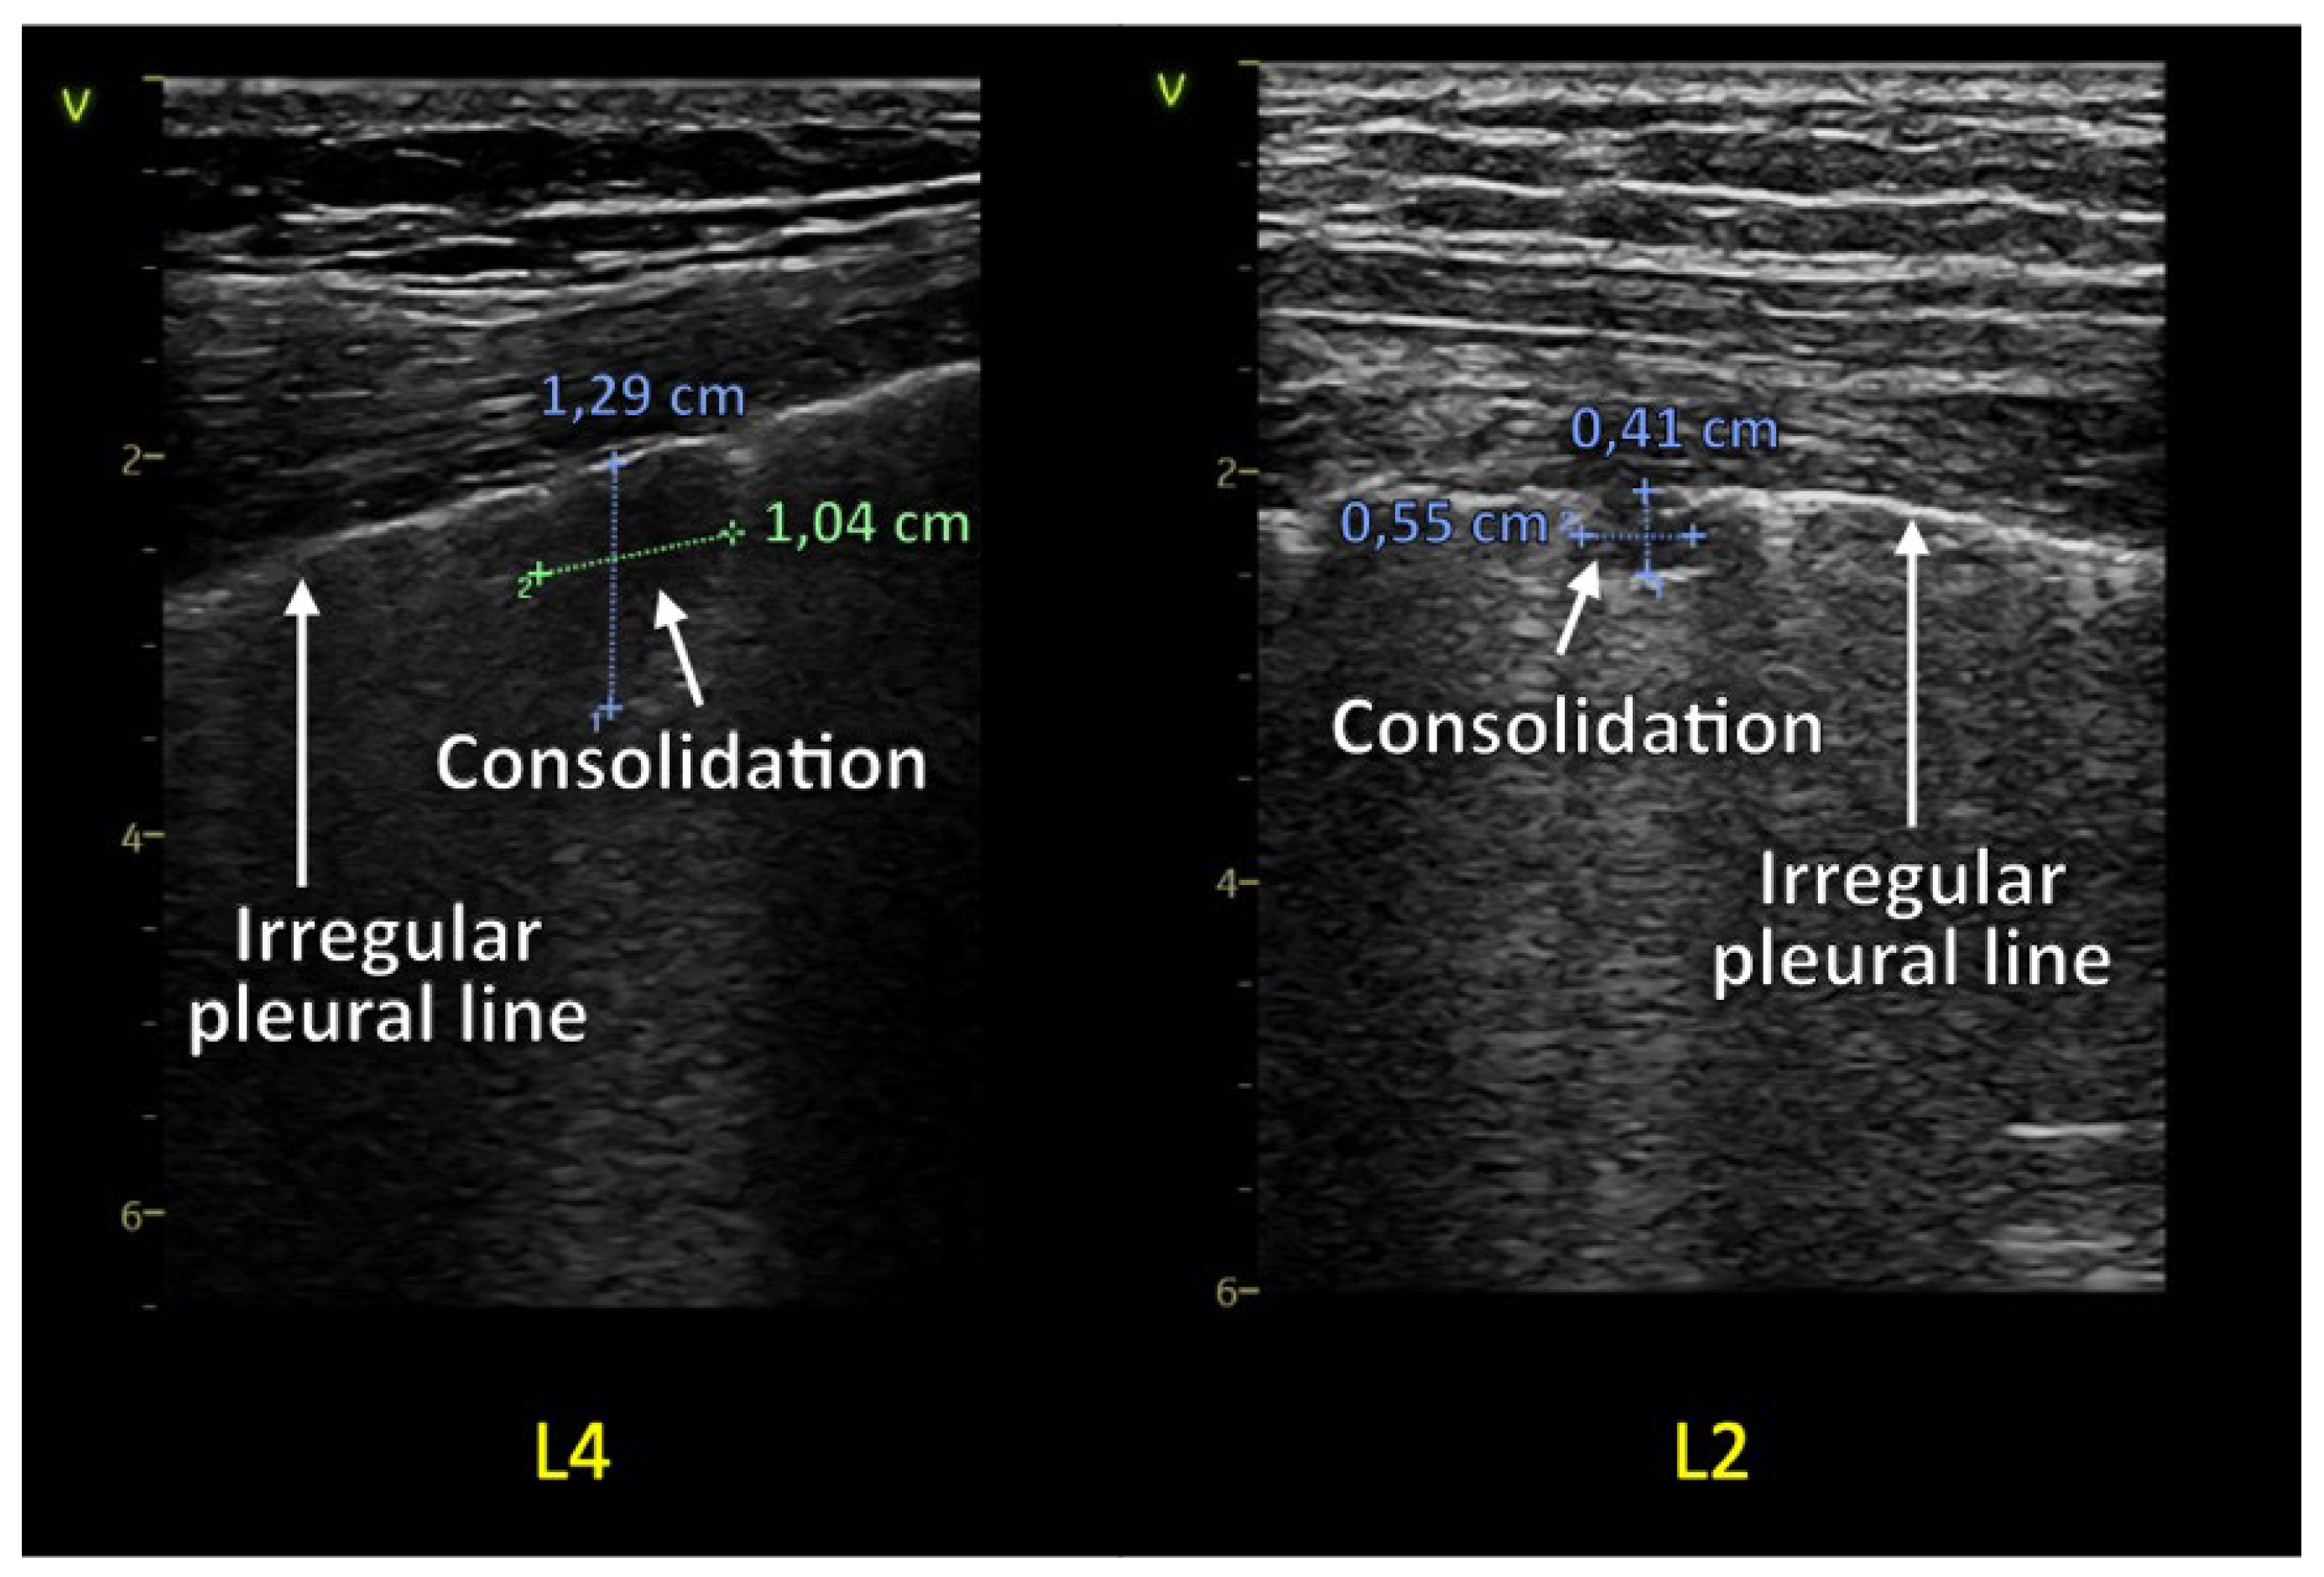

1.1.2. Consolidations and Pleural Effusion

| Zone | N | Consolidations | |

|---|---|---|---|

| 1st Evaluation | 2nd Evaluation | ||

| 1 | R | 1 | 1 |

| L | 0 | 0 | |

| 2 | R | 0 | 0 |

| L | 1 | 0 | |

| 3 | R | 1 | 0 |

| 4 | R | 2 | 0 |

| 5 | R | 0 | 0 |

| L | 0 | 1 | |

| 6 | R | 4 | 0 |

| L | 2 | 0 | |